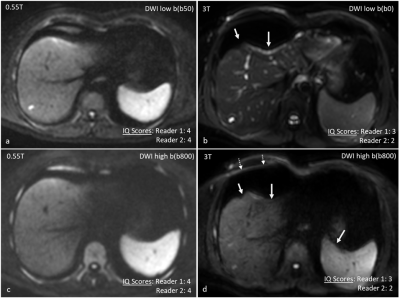

Representative images of DWI (high and low b values) that were rated higher at 0.55T. In comparison to 0.55T (a and c), images at 3T (b and d) had prominent anatomic distortion (solid arrows) and residual aliasing (dotted arrows). DWI was assigned lower scores at 3T by both readers.

DWI parameters at 0.55T: TR/TE= 6000/73 ms, slice thickness= 6mm, FA: 900, ETL:46

DWI parameters at 3T: TR/TE= 1704/68.8 ms, slice thickness= 6mm, FA: 900, ETL: 85